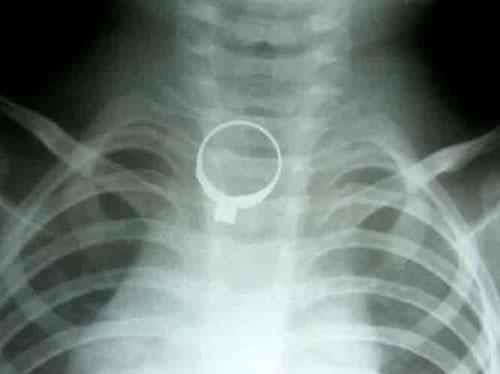

(Cadn.com.vn) - Chiều 25-11, các bác sỹ Khoa Nhi (BV Phụ sản – Nhi) đã tiến hành chạy thận nhân tạo cho bệnh nhi Trần Thị Hoa (12 tuổi), người dân tộc Cơ Tu (trú xã Ba, H. Đông Giang, Quảng Nam). Bệnh nhi nhập viện ngày 17-11 trong tình trạng hôn mê, thở nấc, suy hô hấp nặng, suy tim. Các bác sỹ đã tiến hành cấp cứu kịp thời bằng đặt máy thở và xét nghiệm. Kết quả cho thấy bệnh nhi bị suy đa cơ quan, suy thận nặng, suy gan và đặc biệt rối loạn điện giải.

Kết luận bệnh nhi bị suy thận mạn giai đoạn cuối, cần phải chạy thận chu kỳ hoặc thay thận để kéo dài sự sống. Các bác sỹ chỉ định siêu lọc máu trong 48 tiếng đồng hồ để giải quyết tình trạng nguy kịch. Đến ngày 19-11, sau 48 giờ lọc máu liên tục, bệnh nhi đã tỉnh táo, thở bình thường.

Để giảm chi phí điều trị cho bệnh nhi, các bác sỹ đã tiến hành các xét nghiệm cần thiết và chạy thận nhân tạo chu kỳ cho Hoa, với tần suất 2 lần/tuần, mỗi lần chạy khoảng 2 đến 3 giờ. Chi phí mỗi lần khoảng 2 triệu đồng. Hoa là bệnh nhi đầu tiên được chạy thận nhân tạo tại Bệnh viện Phụ sản- Nhi Đà Nẵng.

| Sức khỏe bệnh nhân Trần Thị Hoa đã ổn định. |